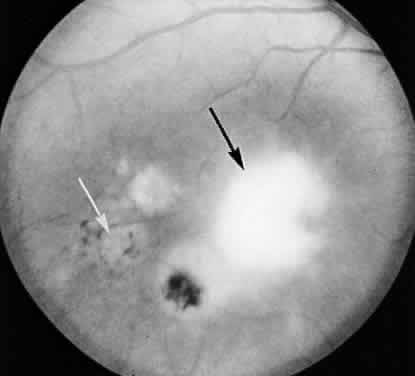

The lesions of ocular toxoplasmosis (Fig. 1) can be important causes of blindness, particularly if they involve the macula, the papillomacular bundle, or the optic nerve. Occasionally, a large peripheral lesion casts off so much inflammatory material into the overlying vitreous humor that vision is affected. In some cases, inflammation initiates organization of the vitreous body; on subsequent contraction of the fibrous bands within this inflammatory mass, tearing of the retina may occur and retinal detachment may ensue.

Fig. 1. The characteristic lesions of toxoplasmic retinochoroiditis in the fundus of an adult. Black arrow denotes active lesion with indistinct borders. White arrow denotes healed “satellite lesions.” (O'Connor GR: Ocular toxoplasmosis. In Locatcher-Khorazo D, Seegal BC (eds): Microbiology of the Eye. St Louis, CV Mosby, 1972.)